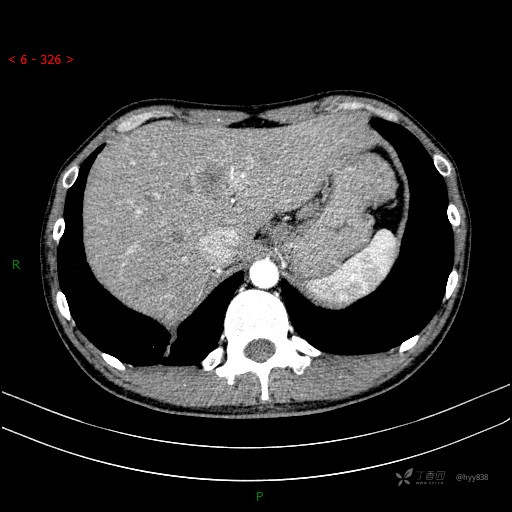

增强动脉期